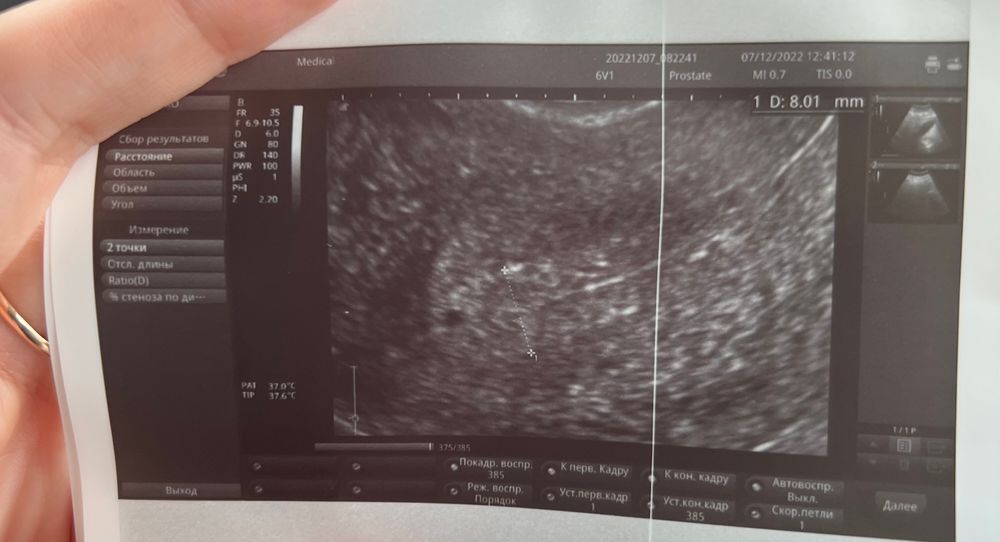

Кистозные включения в эндометрии

У меня после подобных кистозных включений в эндометрии была гистероскопия - в очередной раз вылезли и полипы и гиперплазия. На узи не ошиблась ре в этом плане.

Nata, у меня и до этого бывали полипы , гиперплазии,но на УЗИ таких дырок черных не было в эндометрии...

Nata, и даже не смотря на такую толщину,эти кистозные включения есть гиперплазия?Получается там жидкость какая то?ведь полипы это твердое,а тут как жидкость какая то

Татьяна Газизова, да. Гиперплазия это же больше не про толщину, а про структуру, как мне ре говорила. вот про жидкость не знаю, но в гистологии написано «железистые полипы эндометрия, очаговая гиперплазия эндометрия без атипии»

Nata, а у вас случайно фотки не осталось с этими кистозными включениями?Я сейчас отправила заключение УЗИ врачу,она написала что ничего криминального нет

Татьяна Газизова, а районе дна видно одно включение. Под другими ракурсами датчика были видны еще. Изображение